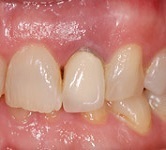

Aspect 5 jours après l'extraction-implantation immédiate

Aspect gingival à 5 jours post-opératoires

Aspect esthétique de la couronne provisoire en résine